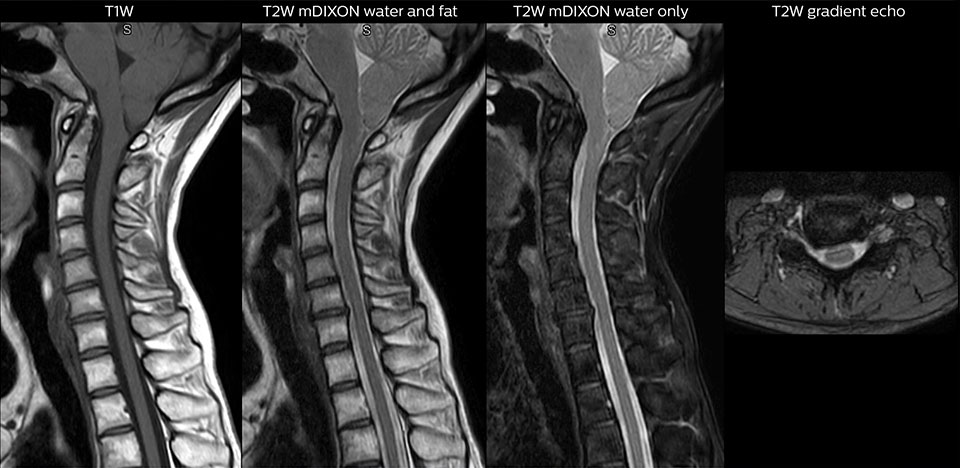

“We use mDIXON TSE extensively in our spine imaging in the emergency room,” says Dr. Karis. “It’s particularly nice in that it is very robust with regard to susceptibility type of problems that would come up with traditional spectral fat-saturated images; these problems are essentially eliminated with the mDIXON technique. In our ED environment it’s really nice to have the fat-free imaging that goes along with the mDIXON technique.

“For the thoracic and cervical spine routine non-contrast exam, for example, we perform one mDIXON T2 TSE sequence, which provides us with two outputs: the fat-and-water-together T2-weighted images, as well as the water-only sagittal T2-weighted images. And then we also perform an axial gradient echo exam.”

Cervical spine routine exam

This patient presented with headache that was worse with neck flexion and we see a Chiari 1 malformation with low-lying cerebellar tonsils as well as some degenerative cervical thrombolytic change.